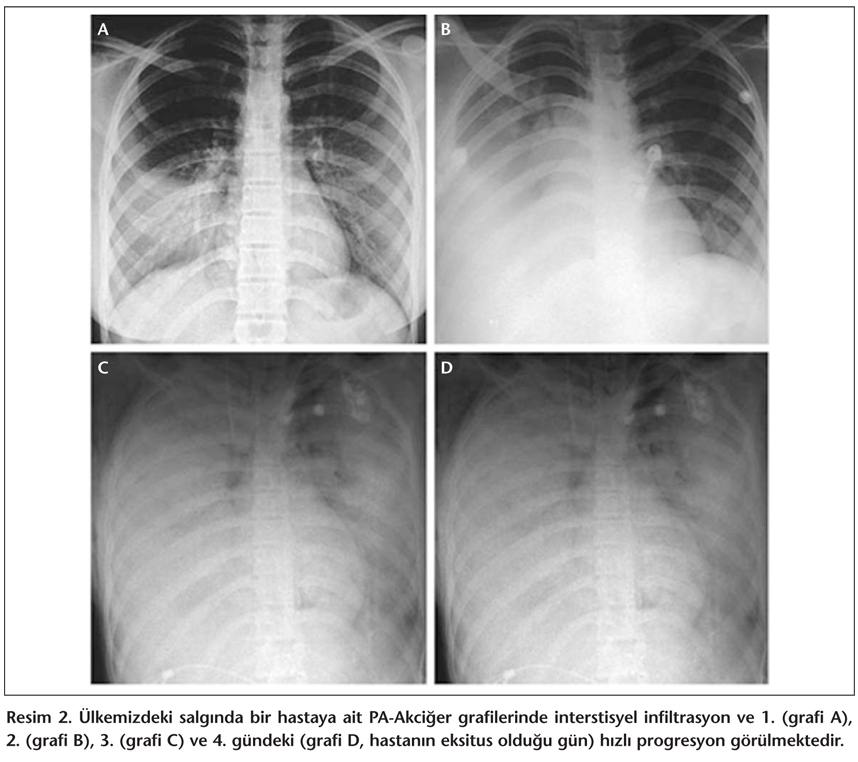

Başlangıç semptomları sonrasında genellikle alt solunum yolu belirtileri gelişir ve hastaların hekime müracaatında bu bulgular mevcuttur[65]. Bir seride hastalığın başlangıcından sonra ortalama beş günde (1-16 gün) dispne geliştiği bildirilmiştir[63]. Solunum sıkıntısı, takipne ve inspiratuar raller yaygındır. Balgam çıkarma değişkenlik arz eder ve bazen kanlıdır. Hastaların hemen hemen tümünde klinik olarak pnömoni mevcuttur. Radyolojik değişiklikler difüz, multifokal yama infiltrasyonlar, interstisyel infiltrasyonlar ve hava bronkogramları ile birlikte segmental veya lobüler konsolidasyon şeklindedir (Resim 1). Bir çalışmada, radyolojik anomaliler ateşin başlangıcından sonraki ortalama yedi gün içinde görülmüştür[63]. Vietnam'da hastaların hastaneye kabulleri sırasında en yaygın radyolojik bulgunun en az iki zonda multifokal konsolidasyon olduğu bildirilmiştir[65]. Plevral efüzyon yaygın değildir. Hayatta kalan hastalarda akciğer hasarıyla ilgili radyolojik bulguların hastalıktan sonraki birkaç ay devam edebileceği vurgulanmaktadır[65].

Ülkemizde sekiz olgunun yedisinde hastaneye başvuru sırasında klinik ve radyolojik olarak pnömoni bulguları saptanmıştır. Bu hastaların akciğer grafilerinde bilateral yaygın infiltrasyon, lober kollaps, fokal konsolidasyon, hava bronkogramları tespit edilmiştir[71]. Resim 2'de ülkemizde kaybedilen bir olguya ait akciğer grafileri yer almaktadır. Resimden de anlaşılacağı üzere bu olguda pnömoni günler içerisinde hızla ilerlemiştir. Ülkemizdeki olguların hiçbirisinde plevral efüzyon saptanmamıştır. Klinik olarak iyileşen dört hastanın ikisinde tek taraflı, bir hastada ise bilateral konsolidasyon saptanmıştır[71].